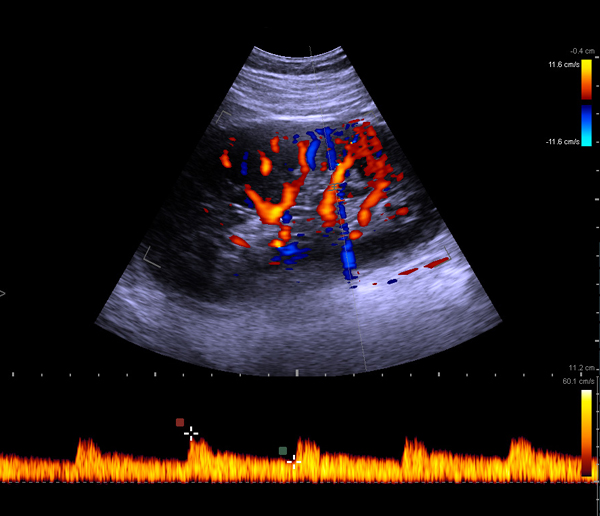

Ultrasound for Kidney

BK Medical systems provide high-resolution image quality for advanced kidney imaging, measurement, and biopsy. See anatomical details and variations and find kidney stones. Visualize and measure blood flow with highly sensitive color Doppler.